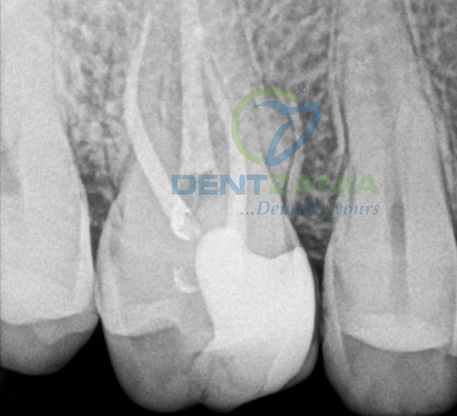

Before / After

1. Diagnosis & X-Ray

X-rays are taken to assess the damage

If the nerve of a tooth has become decayed or infected, a Root Canal may save the tooth itself whilst removing the problematic root. The nerve part of the tooth, along with the pulp (living tissue inside the tooth) and any bacteria or decay present is removed; then the tooth is sealed with special root-filling cement all the way to the tip of the root. This will save your tooth once the root is filled and sealed properly to the very apex; and it gets rid of the painful soft tissue and leaves a hard shell. A dental crown is then fitted to ensure the tooth has full functionality within your mouth.